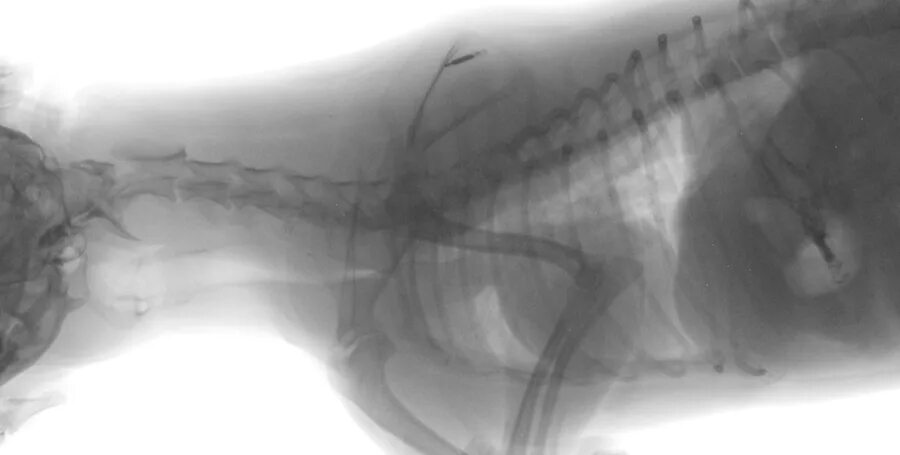

Лимфома у собак симптомы